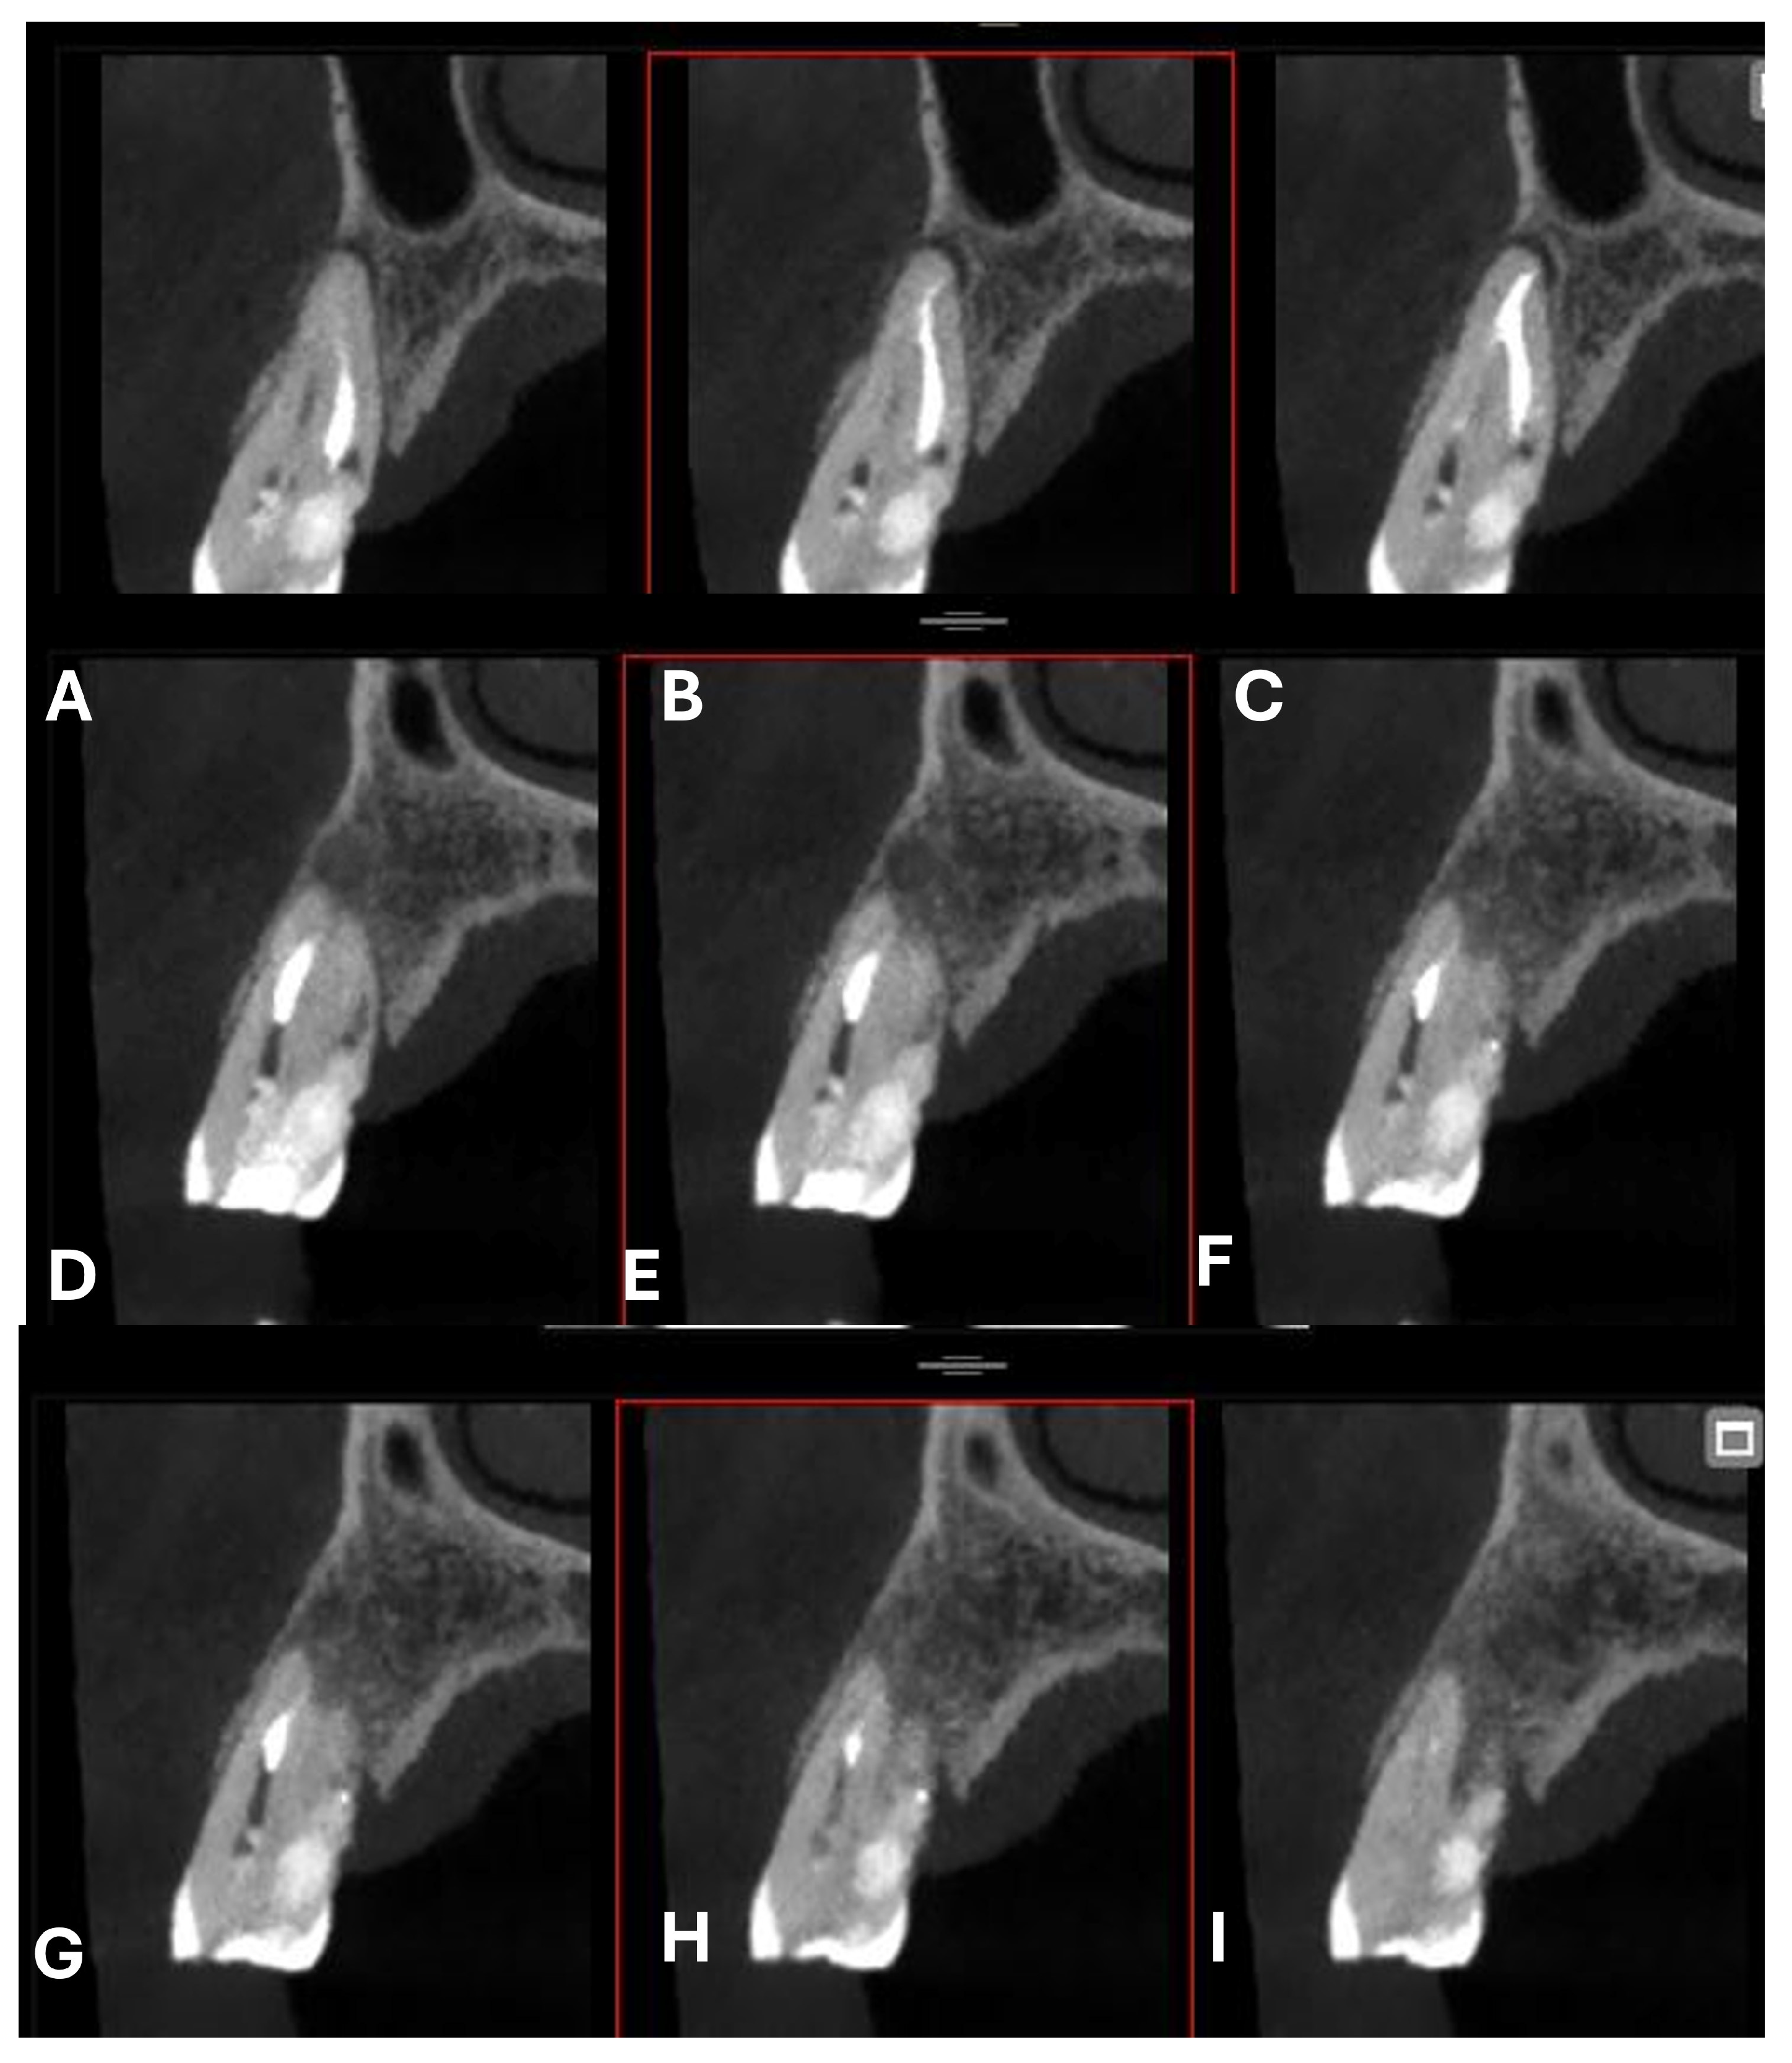

A CBCT examination (X9 Pro®, MyRay, Imola, Italy), performed with dedicated field of view (FOV) (6 × 6) and exposure parameters, was essential for accurate diagnosis and treatment planning. This device optionally features a specific Booster function for users with advanced expertise, which allows for further customization of exposure parameters to optimize the examination more effectively. Optimal management of the FOV, properly centered and limited to the anatomical area of interest, in this specific case slightly extended (6 × 6) to clearly rule out a possible involvement of the maxillary sinus in agreement with the attending otorhinolaryngologist, enabled the acquisition of broader and more detailed clinical and diagnostic information, which is essential in endodontics. Moreover, it allowed for a significant reduction in radiation dose while optimizing spatial resolution [22]. The imaging clarified the extent of the resorption and defined its perimeter, demonstrating an endodontic-periodontal communication, classified as 3Bp according to Patel’s classification [21] (Figure 2, Figure 3, Figure 4 and Figure 5).

Figure 2.

Axial CBCT images of tooth 1.4, showing its ECR and PL. (A–E) Sequential scrolling on the axial plane from the cervical area to the middle third of the root; (F,G) Segmentation of Figure 2E using the advanced software functions iRYS® (MyRay, Imola, Italy); (H,I) Sequential scrolling on the axial plane of the apical third of the root, including the PL.

Cross-section CBCT images of tooth 1.4 after six months of healing. (A–I) Sequential scrolling of EPL healing.

Figure 12.